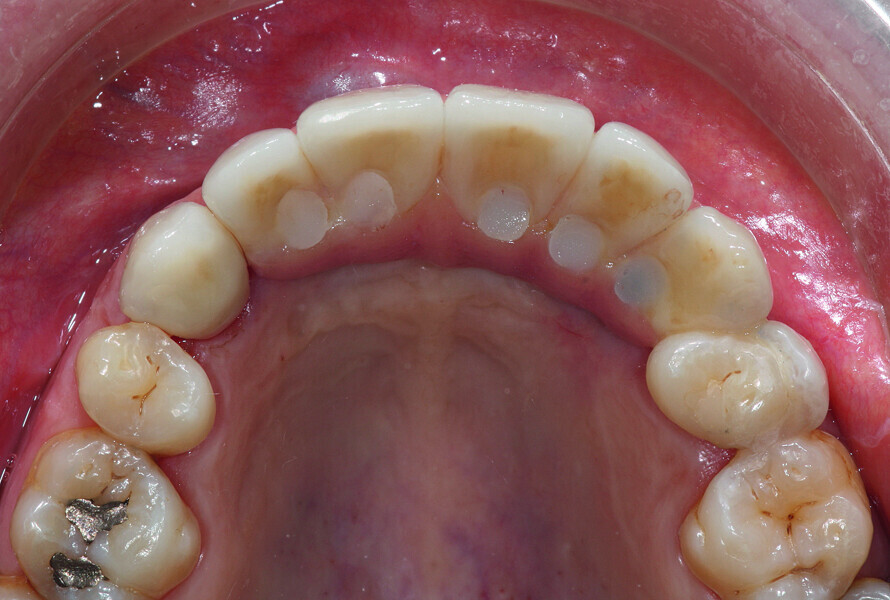

Fig. 38: Final cosmetic check-up showing correct lip support with the new extremely reduced false gingiva.

Fig. 39: Final cosmetic check-up showing correct lip support with the new extremely reduced false gingiva.